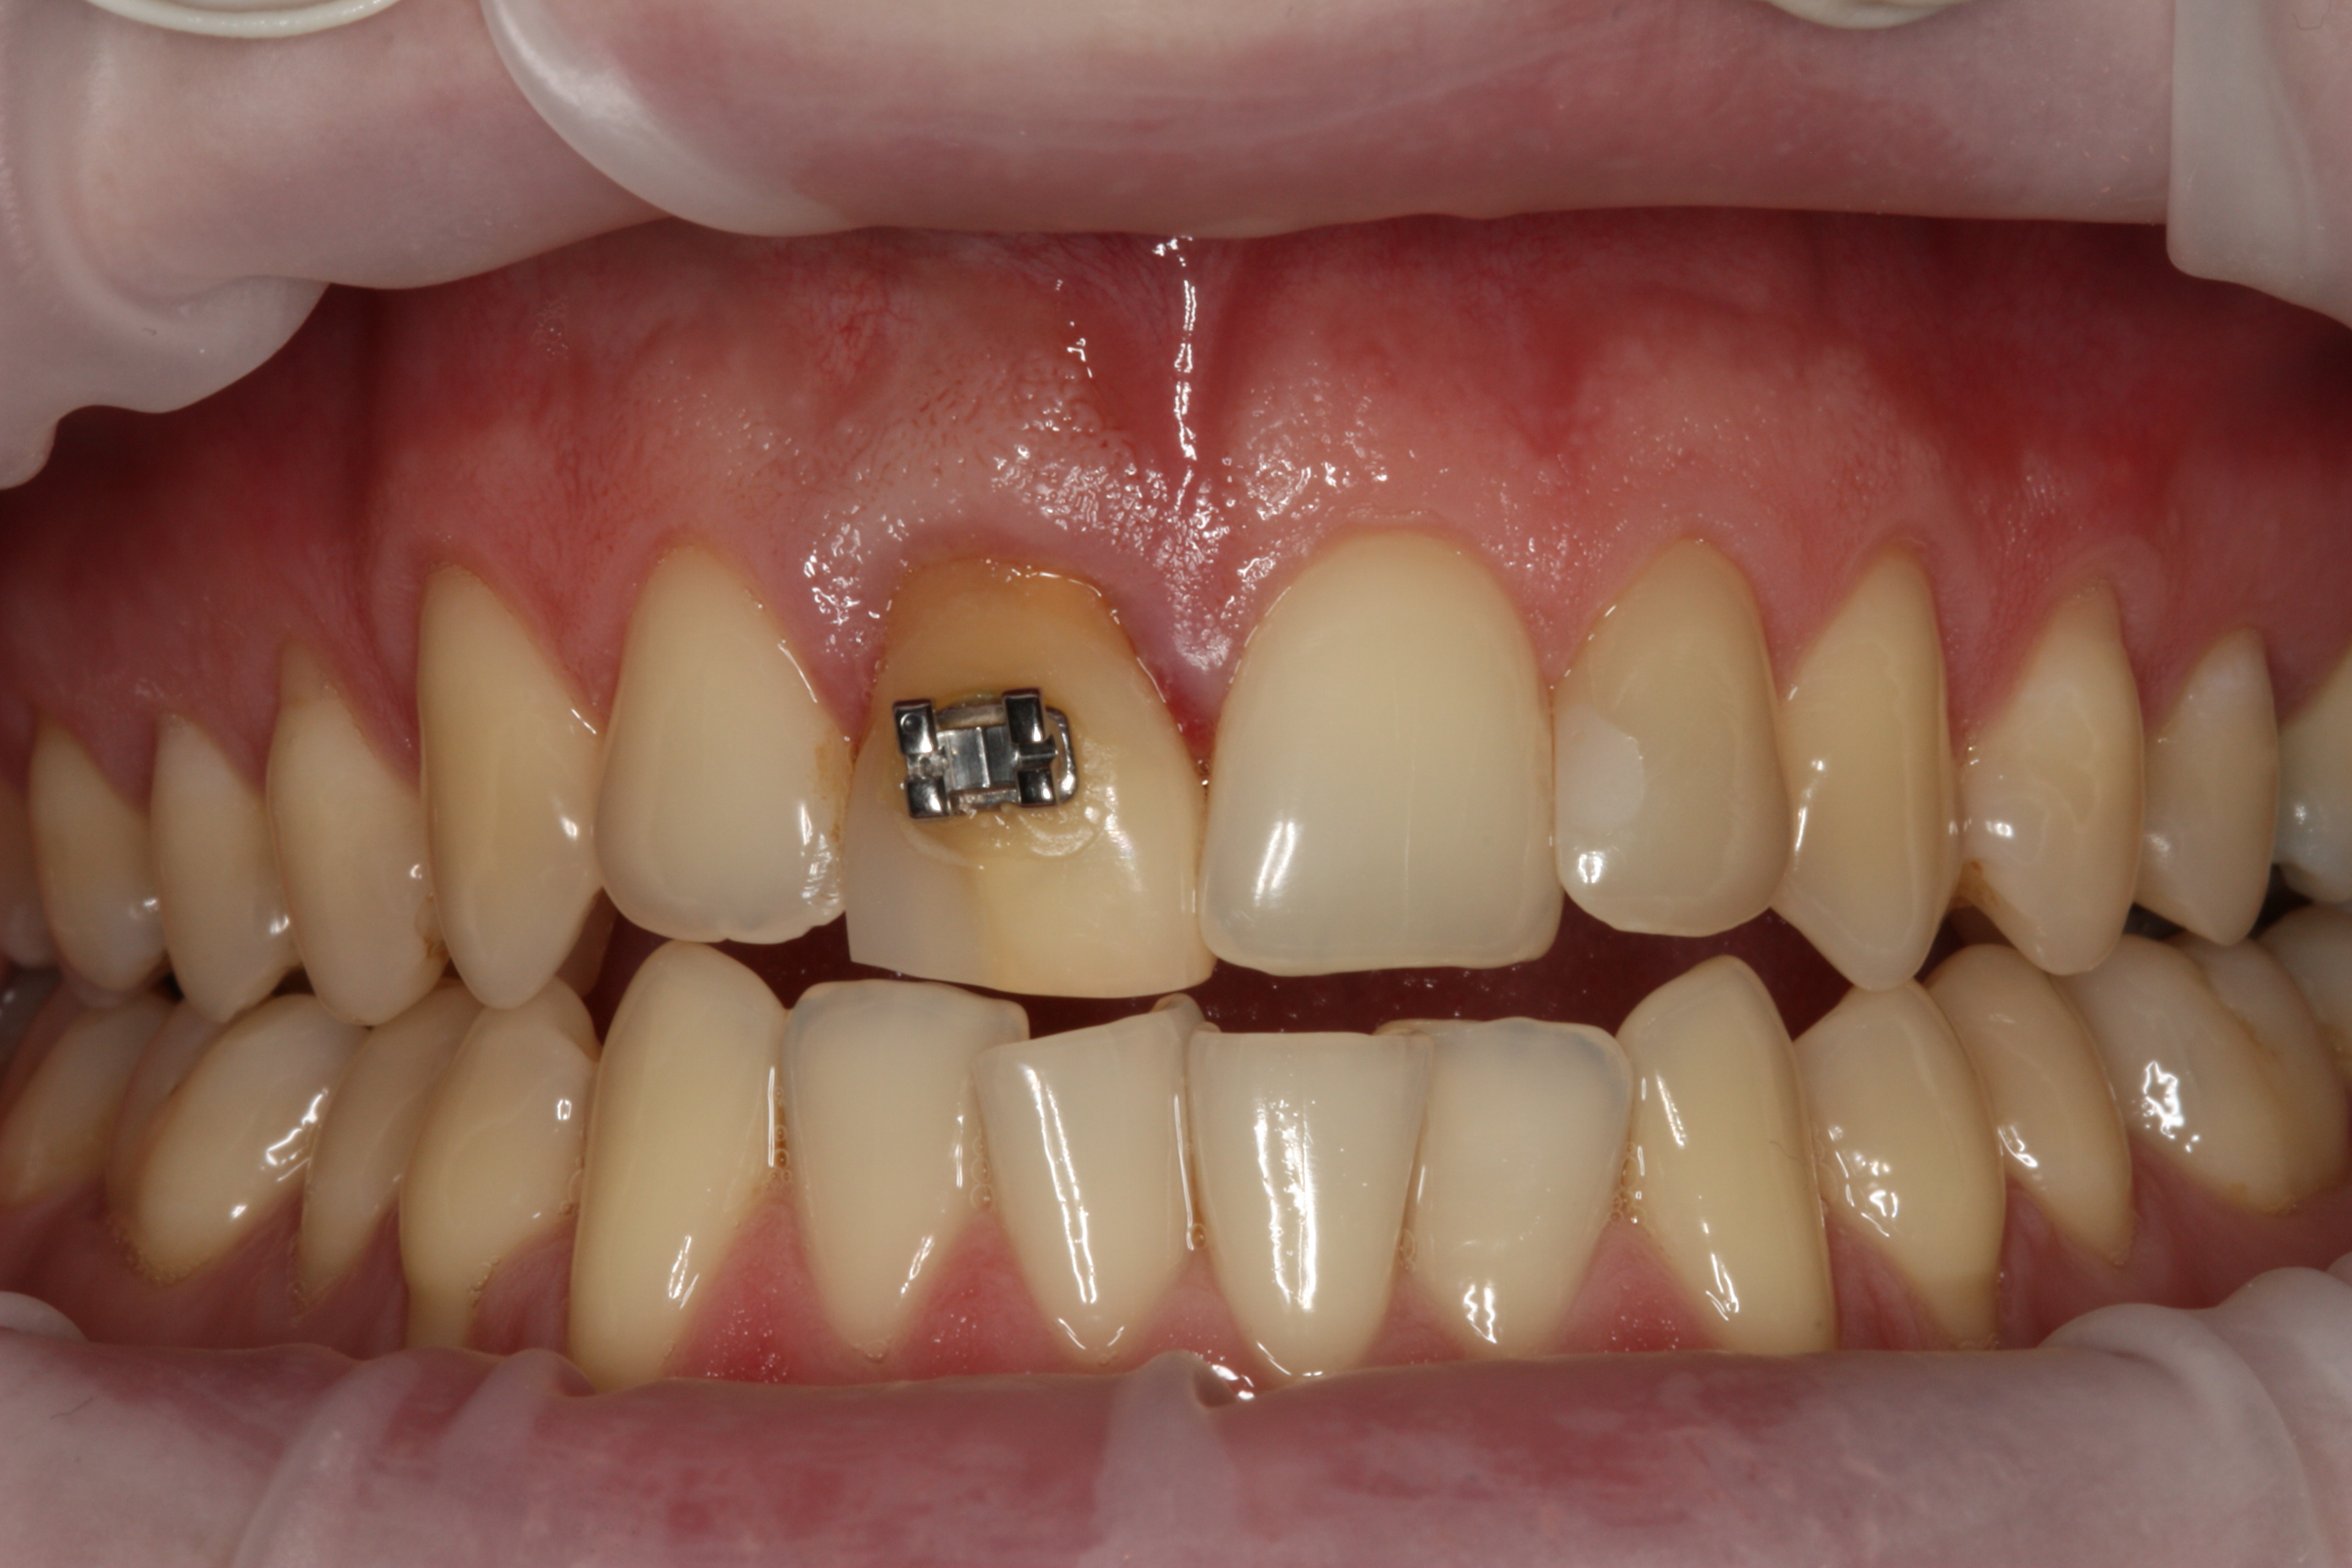

Przykład ekstruzji ortodontycznej za pomocą płytki termoformowalnej i zameczka ortodontycznego: